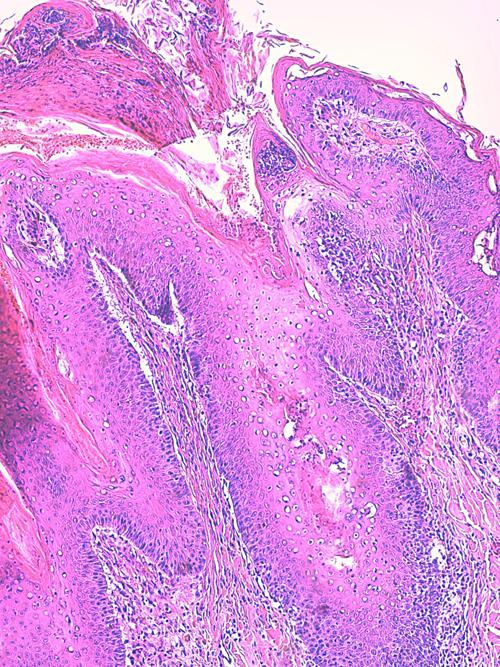

Photo 9 (Hémalun Eosine X 100) peau velue : La couche cornée montre une

stratification de micro-pustules, notamment aux abouchements folliculaires.

Le grand axe d’un infundibulum folliculaire montre une

zone linéaire tortueuse de fissuration et de nécrolyse.

Légendes de la Photo 9 :

- Double flèche pointillée verte : grand axe des infundibula folliculaires

- Double flèche bleue : épiderme

- Double flèche noire : derme

- Ovale jaune : pustules obstruant les abouchements follicualires à l’épiderme

- Flèches jaunes : fissurations linéaires tortueuses cheminant le long des infundibula folliculaires

- Étoiles turquoises pleines : parakératose